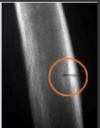

- Rx décrites comme de qualité médiocre, « bougées » à cause de la déminéralisation qui rend l’image flou - Pseudofracture de Loose-Milkman (très caractéristique) - Perpendiculaire à la corticale (axes des os longs) - Lignes radio-transparentes - Présents aux sites de fracture ci-dessus. - Résultent de fractures de stress qui guérissent avec de l’os non-minéralisé.